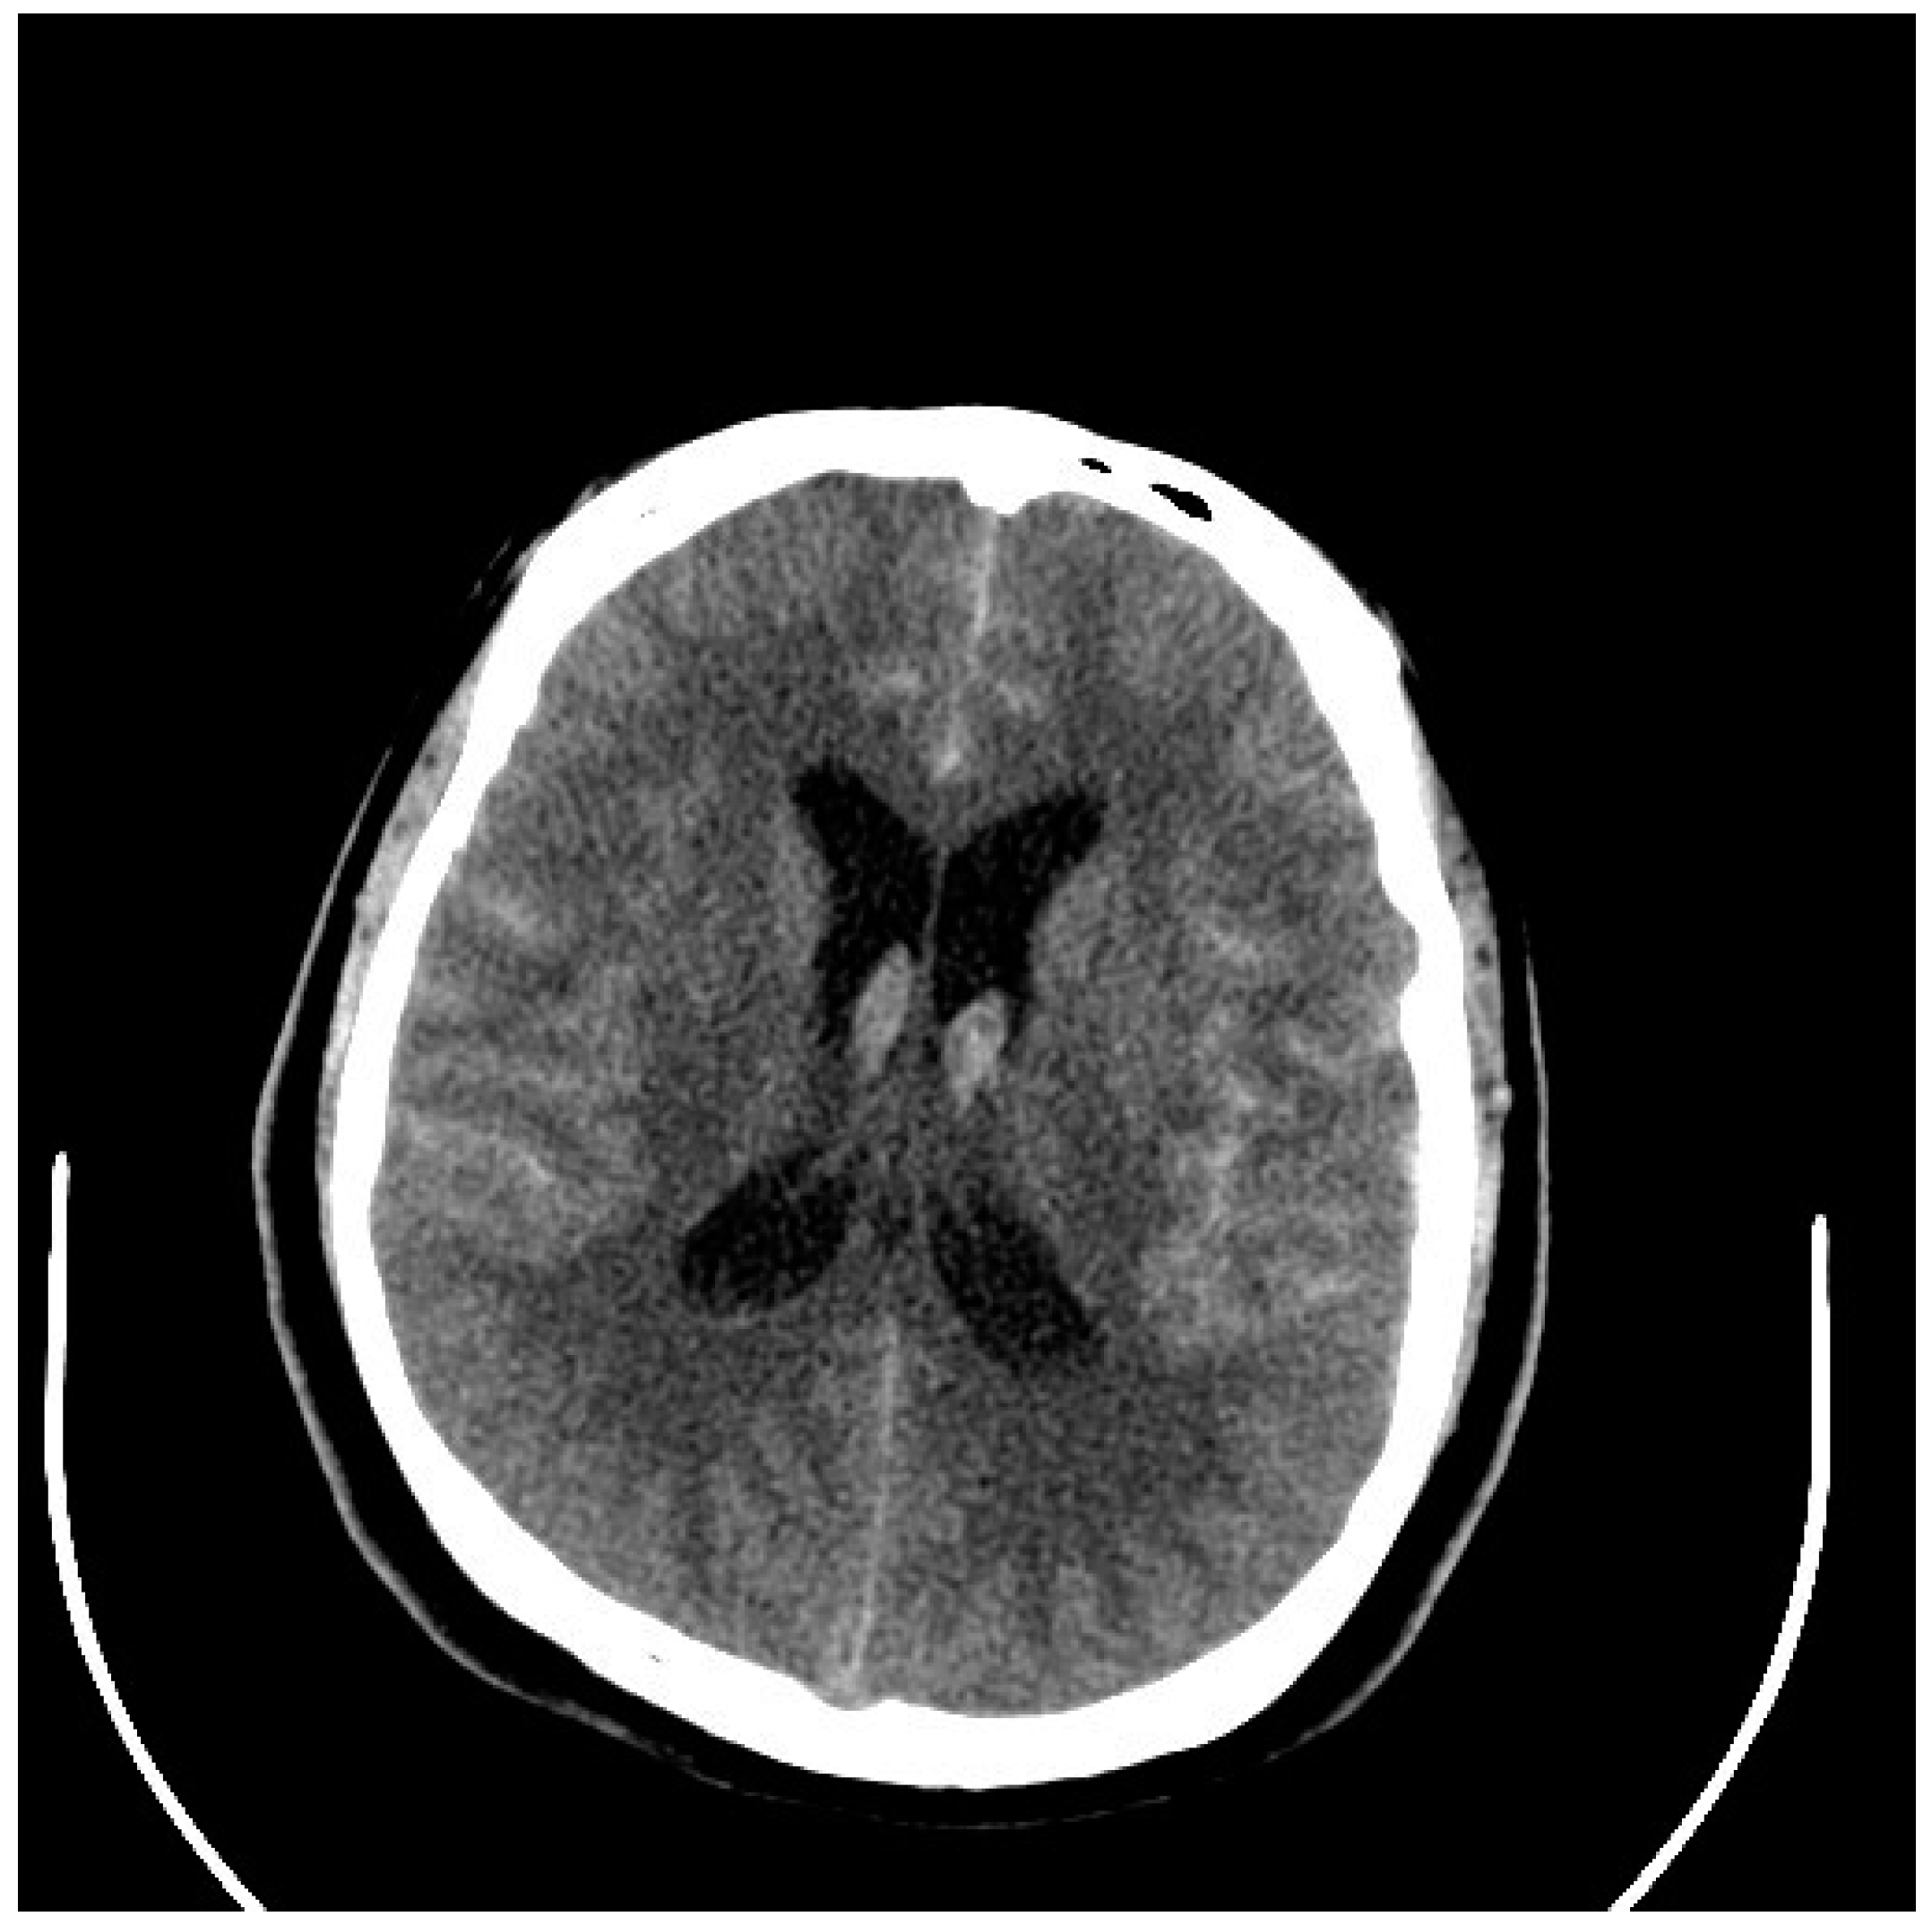

5. Diagnosis